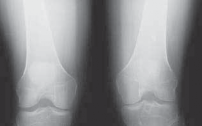

IMAGING AND OTHER DIAGNOSTIC STUDIES

3. Routine radiographs, including weight-bearing anteroposterior and lateral views as well as patellar views, should be performed. In the revision setting, these images allow for critical assesment of previous tunnel placement and assesment for possible bone loss at previous tunnels, which may require further evaluation and treatment.

1. Metallic fixation devices make previous tunnel placement easy to identify, but bioabsorbable screws and other types of fixation also can be evaluated for tunnel placement on these images (

FIG 1

).

2. These images also allow evaluation for possible evidence of osteoarthritis.

FIG 1 • A,B. Anterior cruciate ligament (ACL) reconstruction performed with an EndoButton (Smith & Nephew, Andover, MA) on the femur and staple fixation of the graft on the tibia. C,D. Anterior placement of the femoral tunnel in this primary ACL reconstruction performed with a two-incision technique. A B C

D

13. A common cause of failure related to surgical technique is anterior placement of a femoral tunnel, which often is detected on the lateral radiograph (

FIG 1D

).6,10 This may lead to tightening of the graft with knee flexion resulting in graft stretch-out or failure.